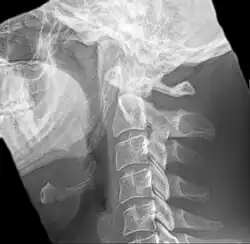

| Anteroposterior and lateral radiographs of cervical spine showing ossification of the stylohyoid ligament on both sides | |

Radiograph, lateral view showing elongated stylohyoid process and stylohyoid ligament ossification -

Radiograph, lateral view showing joint-like formation in ossified stylohyoid ligament -